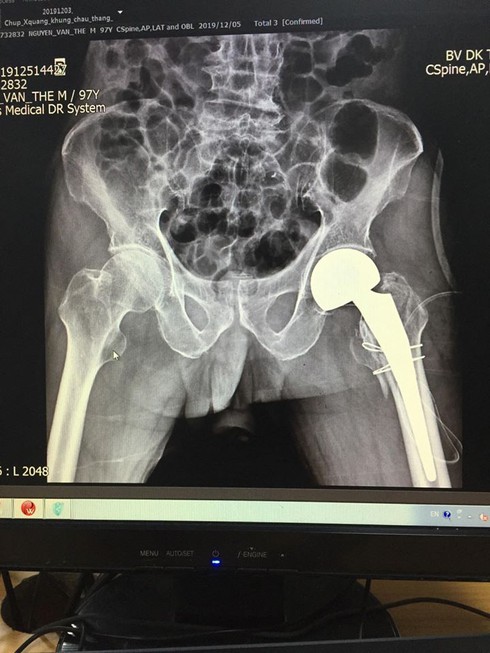

Khớp háng bị gãy của người bệnh trên phim. |

Ngay lập tức người bệnh được các bác sĩ thăm khám và chỉ định các xét nghiệm, chụp chiếu, hình ảnh chụp X-quang cho thấy người bệnh bị gãy liên mấu chuyển xương đùi. Tiến hành hội chẩn liên khoa: Tim mạch, Gây mê, Chấn thương I; sau khi đánh giá toàn diện được chỉ định thay khớp háng bán phần không cement.